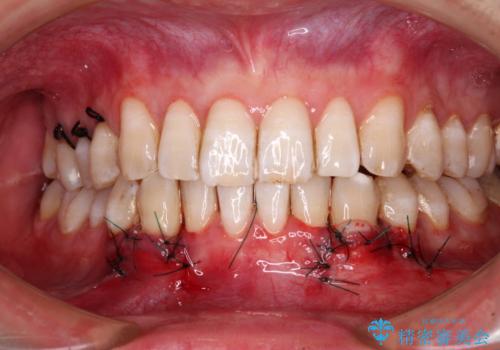

歯肉移植により根面被覆が達成されるとともに、歯肉が厚みを増したことで、今後の歯肉退縮リスクを軽減させることができました。

- 外科手術のため、術後に出血、痛みや腫れ、違和感を伴います

- 口腔内の状態によっては適応できないことがあります